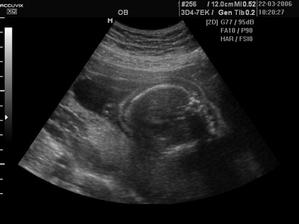

Náš pokladík Viktorko sa narodil 28.7.2006 o 19:20. Vážil 3650 g a meral 52 cm 😉.